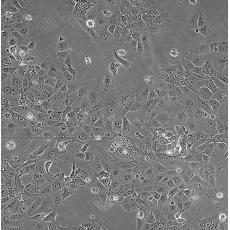

中文名稱 人非小細(xì)胞肺癌細(xì)胞

組織來(lái)源 肺腺癌;女性

生長(zhǎng)特性 adherent

形態(tài)特征 epithelial

細(xì)胞描述 This lung adenocarcinoma has an acquired mutation in the EGFR tyrosine kinase domain(E746-A750 deletion).